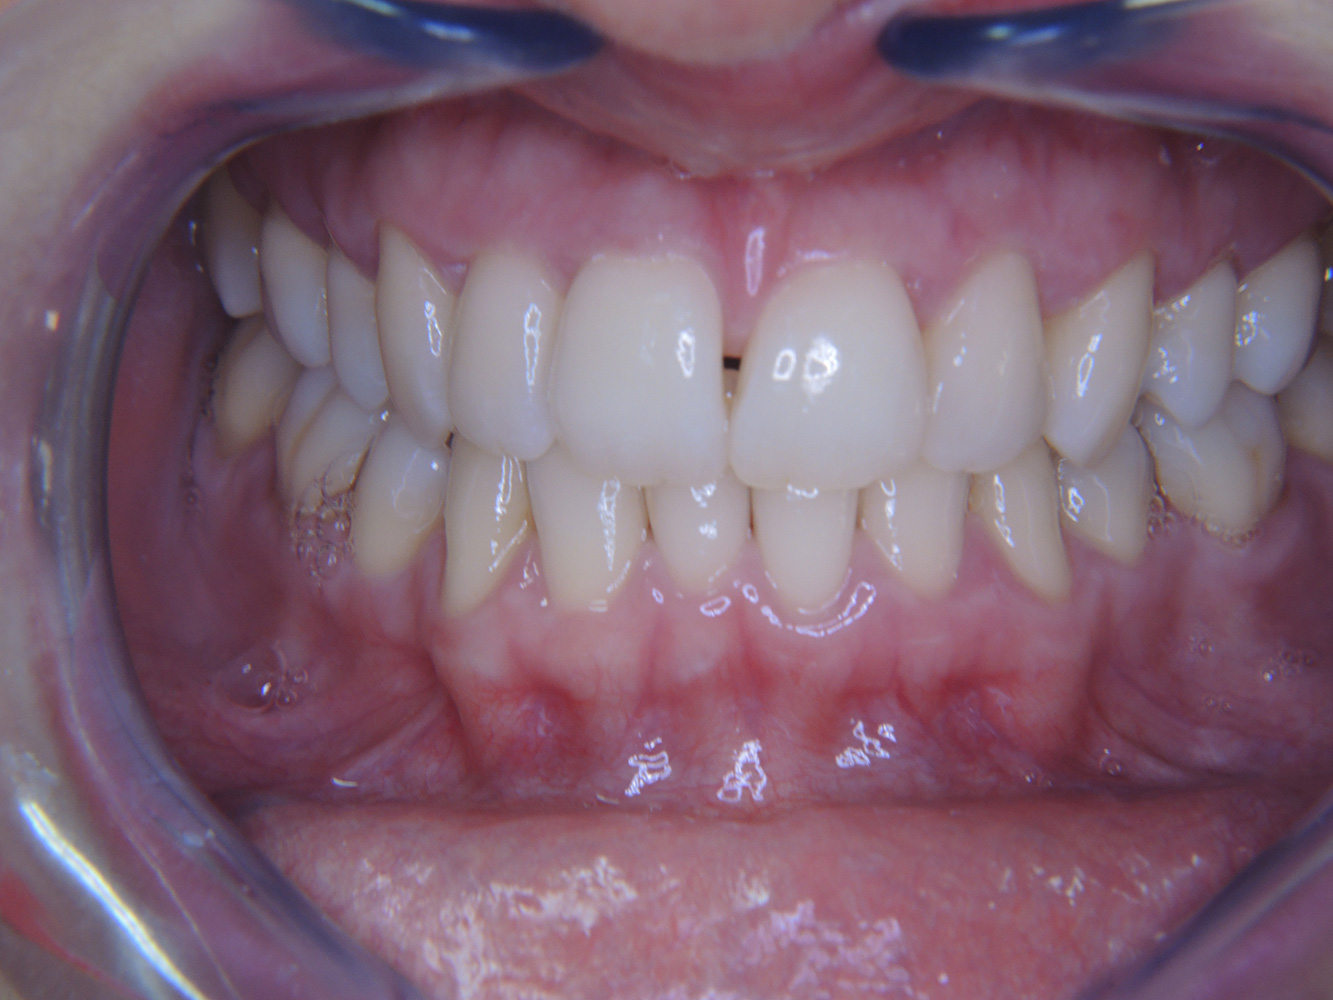

The direct relationship between intraoral and general health, as well as the bidirectional influence that they may have on one another, is well-known (1,2). It is absolutely essential to consider both factors when planning preventive intraoral measures and treatment in the dental practice. The primary objective is the maintenance of patient health and quality of life from both dental and medical perspectives. more

The (orally) healthy patient with implants

In the medical history, the 55-year-old patient states that he has no systemic disease and is not taking any medication. The patient’s lifestyle is similarly unremarkable. The patient has a few tooth restorations and two implants (2nd and 4th quadrants). On the basis of current findings, gingivitis is identified in an otherwise stable periodontal condition on the reduced periodontium (stage III, grade A). more